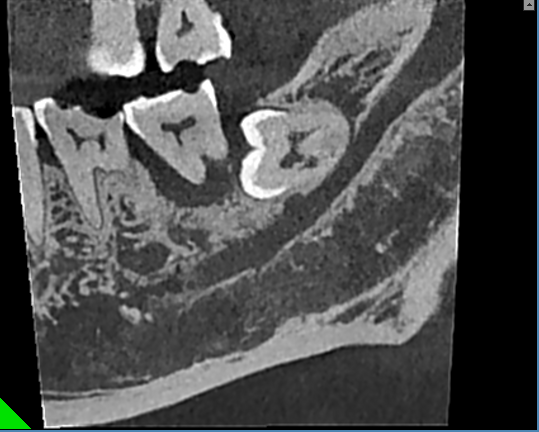

残根